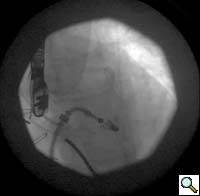

4. From the right femoral venous puncture, a TEE guided trans-septal puncture of the septum is performed using a standard transseptal kit (Figure 7) with the Brockenbrough needle, a dilator and a Mullins sheath. The site of the puncture is decided using a standardized approach which optimizes the maneuverability of the delivery system. The puncture is usually high and posterior in the fossa ovalis. After successful septal puncture, the Mullins sheath is parked in the left atrium and the patient is heparinized to achieve an ACT of at least 250 seconds.